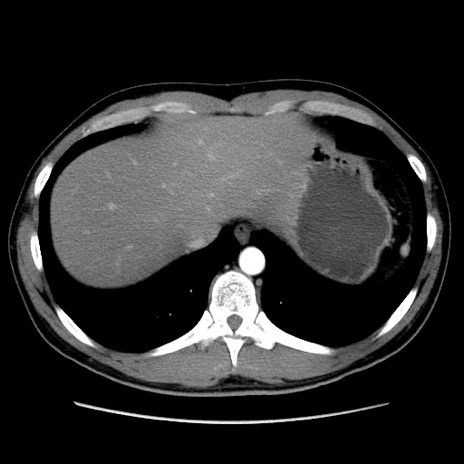

症例36(横断像)

【症例】20歳代 男性

【主訴】心窩部痛

【現病歴】今朝より上腹部痛あり。一旦軽快していたが再度出現したため救急要請。昨日夕に白身の魚を含む刺身を食べた。

【身体所見】BP 136/89mmHg、HR 74/min、BT 37.0℃、腹部:膨満、軟、心窩部に圧痛あり。反跳痛なし、筋性防御なし、腸雑音やや亢進あり。

【データ】WBC 17700、CRP 0.48